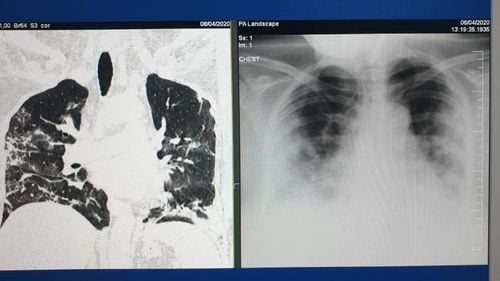

FOTO  Medic aflat în prima linie în lupta anti-Covid: ”Nu mai pot citi mesajele celor care neagă în continuare existența Covid-19 sau spun că e o simplă gripă care trece!" / Cum arată plămânii unor tineri fără alte afecțiuni după ce s-au infectat cu coronavirus

FOTO  Medic aflat în prima linie în lupta anti-Covid: ”Nu mai pot citi mesajele celor care neagă în continuare existența Covid-19 sau spun că e o simplă gripă care trece!” / Cum arată plămânii unor tineri fără alte afecțiuni după ce s-au infectat cu coronavirus